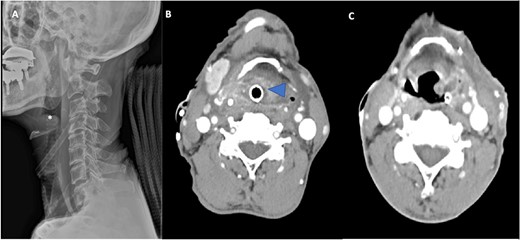

A 72-year-old man with diabetes presented to the emergency department with dyspnea, stridor and odynophagia that suddenly started 3 h earlier. Clinical examination revealed that the patient was febrile with hypoxia, hoarseness and drooling. Flexible fiber optic rhinopharyngo-laryngoscopy showed pooling of secretions in the pyriform sinuses, a swollen and edematous epiglottis, poor visualization of the glottis and reduced vocal cord movement. A lateral neck radiograph revealed a swollen epiglottis and, due to his respiratory distress, the patient was intubated by the emergency physician in the emergency room; CT of the neck with intravenous contrast revealed a multiloculated abscess involving the epiglottis, and paraglottic as well as parapharyngeal spaces (Fig. 1A and B). Laboratory workup revealed an elevated white blood cell count and inflammatory markers. The patient was transferred to the operating room for microlaryngoscopic examination, combined transoral and transcervical incision, neck abscess drainage and tracheostomy. A Klinssaer laryngoscope was used to expose the supraglottic and glottic regions. A gush of pus was observed during laryngoscope insertion into the vallecula and epiglottis, and two small incisions were made at the level of the ventricular folds using a laryngeal knife (Fig. 2A). A swab was collected and sent for bacteriological and mycological examination. The tissue biopsies were performed using cup forceps. Subsequently, a transcervical approach to drain the left parapharyngeal space was begun, with an incision made two fingerbreadths below the left mandible, after which the subplatysmal flaps were elevated superiorly and inferiorly. The parapharyngeal space was accessed after medial retraction of the submandibular gland and dissection above the posterior belly of the digastric muscle, where pus collection was drained. Warm saline irrigation in addition to diathermy was used to achieve hemostasis, and a negative pressure drain system was inserted prior to multilayer wound closure. Finally, a tracheostomy was performed utilizing a 2-cm anterior neck incision at the level of the third tracheal ring. At the end of the procedure, a nasogastric tube was inserted to ensure enteral feeding during the recovery period. After an infectious disease consultation, the patient was started on ceftriaxone and metronidazole for 1 week. Marked improvement in the patient’s symptoms was observed. The flexible scope showed improved visualization and mobility of the supraglottic and glottic areas (Fig. 2B and C), and decannulation was performed on day 4 after passing a trial. A CT scan repeated 1 week post-operatively revealed marked resolution of the abscess (Fig. 1C). The patient was administered oral antibiotics for another week. Clinical follow-up after 1 month was unremarkable.

(A) Lateral radiograph of the neck shows a swollen epiglottis (*). (B) Computed tomography axial cut shows a collection in the paraglottic space (arrowhead) and parapharyngeal space extenuation with effaced pharyngeal and supraglottic lumina due to epiglottic enlargement. (C) Computed tomography axial cut at Day 7 post-operatively reveals a marked reduction in the size of the collection.